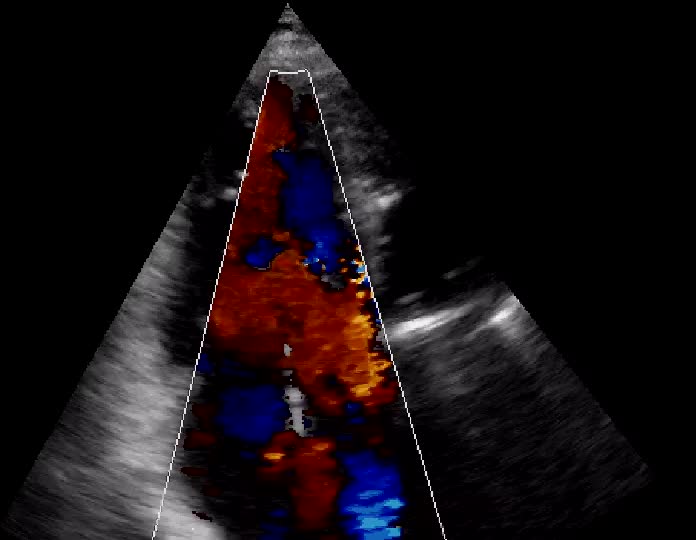

Insufficienza tricuspidale severa

Daniela Torta

Antonio Mantero